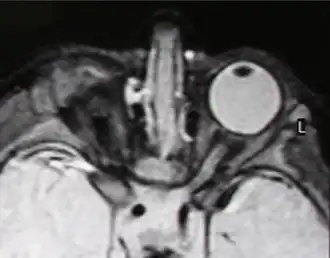

| Правосторонняя анофтальмия (МРТ-изображение) | |

Анофтальм, анофтальмия (от др.-греч. ἀν- — отрицательная приставка и ὀφθαλμός — глаз) — недоразвитие, либо же отсутствие глазного яблока. Встречается как истинная анофтальмия, так и мнимая. Истинная, как правило односторонняя, связана с недоразвитием переднего мозга или с нарушением отхождения зрительного нерва на периферию в процессе развития. Причиной мнимой анофтальмии является задержка развития глазного яблока. На краниограмме при истинной анофтальмии зрительное отверстие отсутствует, при мнимой оно всегда имеется. Анофтальмия обусловлена рецессивным аутосомным геном. У гомозигот по этому признаку глазные яблоки отсутствуют, у гетерозигот они значительно меньше, чем в норме. По статистике анофтальм встречается у одного из 10000 человек.